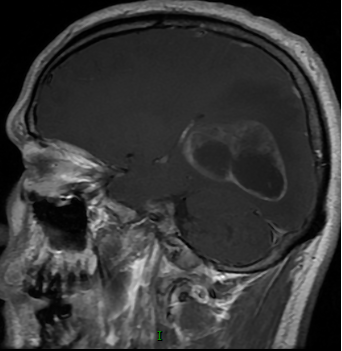

患者中年男性,因“颈部发紧、活动受限伴头晕近半月”入院。PE:NS(-)。头颅MRI平扫+增强检查示右颞枕叶椭圆形囊性肿物,边界清楚,信号均匀,病变周围可见片状水肿,中线结构略向左偏;增强扫描囊壁不规则环状强化(图1)。